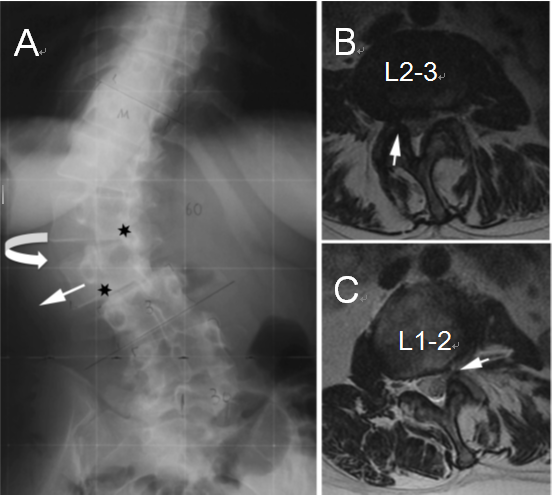

成人脊柱侧凸的腰椎退行性改变也可能会导致椎管或椎间孔的狭窄。超过90%出现神经根疼痛的患者在MRI或CT上出现椎间孔或侧隐窝狭窄,并且通常位于椎间隙出现旋转和半脱位的节段。Gardner等在其文献报道中对侧向半脱位引起的狭窄提出了两种模式:开放性半脱位与闭合性半脱位。在开放性半脱位中,椎间隙在凸侧的张开使椎间盘在对侧突出,这种模式导致对侧(即凹侧)的侧隐窝和椎间孔出现狭窄。 在闭合性半脱位时,椎间盘朝侧向移位侧突出,而导致同侧侧隐窝与椎间孔出现狭窄。笔者认为,充分理解成人脊柱畸形的各种症状的发病机制,将有助于更好的识别成人脊柱畸形患者的症状来源,确认疾病的责任病灶,从疾病根源处解决患者的诉求。尽可能用最小的手术实现最大的症状缓解与功能改善,避免扩大手术范围而破坏脊柱的生理状态,导致翻修手术一而再再而三的发生。

(A)腰椎X线片显示椎体在L1-L2处旋转,椎间盘向凹侧突出,在L2-L3处出现侧向半脱位,椎间盘向凸侧突出;星号表示狭窄部位

(B)轴向MRI显示L2–L3处的凸侧椎间孔狭窄,形成开放性半脱位

(C)L1–L2处的凹侧椎间孔狭窄,形成闭合性半脱位。